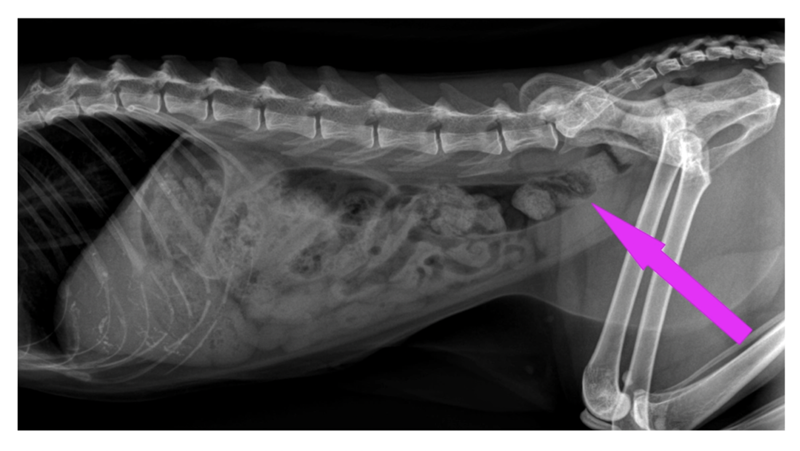

The red arrows indicate two areas of fat pockets (there is more below the pink arrow, however we aren’t as concerned with that for the purpose of this blog). Notice the compression on the stomach, intestines and colon (plus the other organs above and beside those are hard to even see). Also note that the fat pockets will also be pushing into the chest cavity compressing the area available for the heart and lungs.

The pink arrow indicates the colon which has an uphill “S” shape making it so that the body has to work harder to move fecal matter out. This is part of why overweight cats often have issues with constipation.

Looking at this x-ray it may not seem too bad, but let’s compare to a cat that is at a nice lean weight: